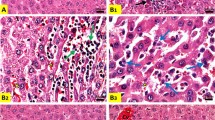

Histolopathological findings showed normal organized hepatocytes forming radiating hepatic cords around the central vein, with normal hepatic tissues including blood sinusoids and portal structures that observed in tissue sections from control saline, LP, and NAC-treated rats. In contrast, we observed severe alterative changes in the hepatic parenchyma, including loss of normal arrangement of hepatic cords, congested central vein and sinusoids, a foamy vacuolated cytoplasm and marked degenerative changes associated with severe nuclear pyknosis that noticed in sections of CP treated rats. Interestingly, LP, NAC, and their combination notably restored the usual hepatic architecture (Fig. 1).

Histopathological changes in liver sections. (a)–(c) Normal organization of the hepatic cords (thick arrow), blood sinusoid (thin arrows), and central vein (CV) of the liver in the control (a), LP (b) and NAC (c) groups. CP-induced changes in the liver include severe degenerative changes, such as loss of normal hepatic cords arrangement, vacuolation (thin arrows), foamy appearance (thick arrow), and pycnotic nuclei of some hepatocytes (S). (e) CP-induced loss of normal cellular architecture of hepatic cords with severe hepatic vacuolation (thick arrow), dilated blood sinusoid (thin arrow), and pycnotic nuclei of hepatocytes (short arrow). (f) histological changes in the liver in the LP + CP group. Moderate effects in the liver include congested blood vessels (CV), dilated blood sinusoid (thick arrow), and condensation of nuclear chromatin of hepatocytes (thin arrow). (g) Histological changes in the liver in the NAC + CP group. Moderate effects in the liver include congested CV, hydropic degeneration (thin arrows), and degranulated cytoplasm of hepatocytes (thick arrow). (h) Histological changes in the liver in the LP + NAC + CP group. Mild effects in the liver include dilated blood vessels (CV) and blood sinusoid (arrows). Scale bar = 50 μm.